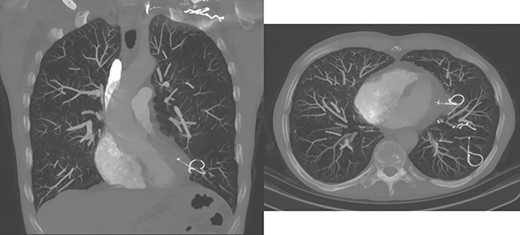

A 61-year-old man presented with 2 weeks of pleuritic chest pain and small-volume haemoptysis. He had undergone left lower lobe endobronchial coil insertion 6 months prior. Computed tomography scanning revealed perforation of the lung parenchyma and mediastinal pleura by an endobronchial coil (Fig. 1), with its tip penetrating the pericardium and abutting myocardium. Trans-thoracic echocardiography demonstrated a sub-centimetre pericardial collection along the inferior cardiac wall without cardiac tamponade.